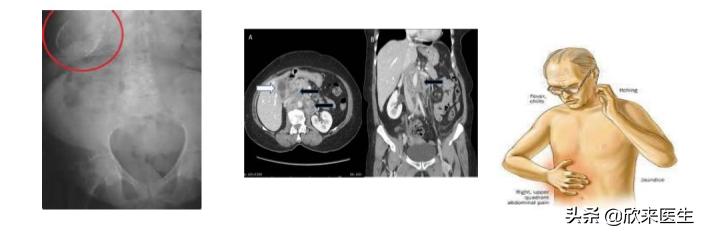

对于有上述状况的人,一般而言,大部份出现胆囊息肉的人都没有明显的症状,如果情况较严重者,可能会出现类似胆囊炎或胆结石的症状,例如恶心、呕吐、上腹胀气、右上腹隐痛,少数甚至还会出现疼痛放射到右肩的情形,就需要进行胆囊切除术的外科会诊,如果没有胆囊切除术,每年随访是必须的。

美国放射学会的指南将有临床症状、年龄>50岁、息肉直径>10毫米、局灶性胆囊壁增厚>3毫米、合并胆囊结石作为手术指征,凡是出现上述指征的胆囊息肉,均建议手术切除胆囊。

情况严重出现类似胆囊炎或胆结石的症状

至于前文所提到的胆囊腺瘤,如果是反复发作、囊壁不规则增厚、60岁以上的患者,也都应该尽早行手术切除。至于如果确定是恶化成胆囊癌,则可以采取先进的腹腔镜胆囊切除以及传统开腹胆囊切除两种手术方式,目前也有 内镜保胆息肉切除术治疗胆囊息肉,还需要进一步探讨 。